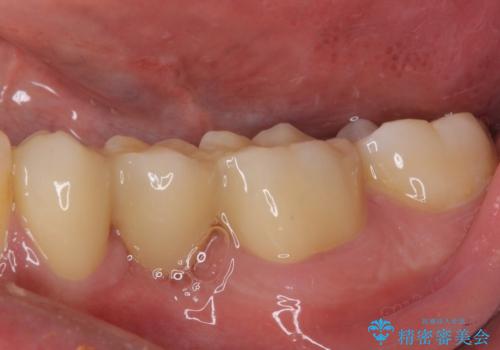

オールセラミックブリッジとしたことで、審美的かつ外れにくい補綴治療を行うことができました。